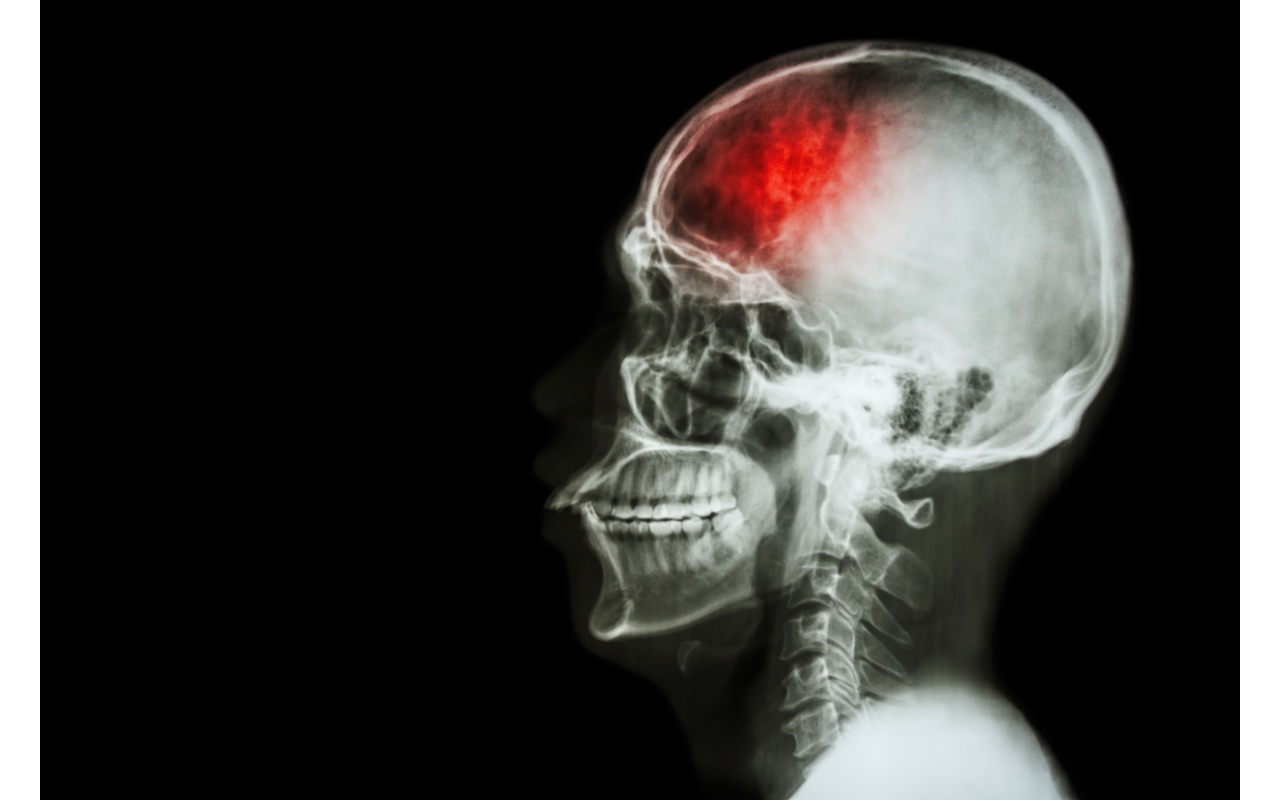

Una nuova ricerca svela il potere del rame sulla salute del cervello. Una giusta quantità di questo metallo, assunta tramite la dieta e/o altre terapie di supporto, potrebbe aiutare la popolazione anziane a rimanere lucida, soprattutto dopo un ictus. È quanto sembra dimostrare un recente studio su Scientific Reports.

Esiste una relazione tra assunzione di rame nella dieta e funzione cognitiva negli anziani? È il quesito cui ha cercato di rispondere un recente studio osservazionale cinese, condotto su una popolazione adulta, americana, di età avanzata, in cui si sarebbe dimostrato che un maggiore apporto di rame, introdotto tramite la dieta potrebbe contribuire a migliorare funzione cognitiva, soprattutto negli individui con una storia di ictus.

Un altro dato rilevante è emerso dall’analisi di specifici sottogruppi: lo studio sembra dimostrare che l’impatto positivo dell’assunzione alimentare di rame sulla funzione cognitiva globale sia particolarmente efficace e sensibilmente superiore in partecipanti con una pregressa storia di ictus. Nello specifico, l’aumento del punteggio Z cognitivo globale in questo gruppo è risultato statisticamente significativo (p per interazione = 0,009).

Le prove esistenti sembrano indicare una efficacia protettiva del rame nel ridurre il rischio di ictus e nell’attenuare il danno neuronale nell’ictus ischemico. Ciò potrebbe essere dipendente dal fatto che il rame, come cofattore per gli enzimi antiossidanti, aiuta a ridurre la produzione di radicali liberi e a prevenire il danno lipidico ossidativo nel cervello.